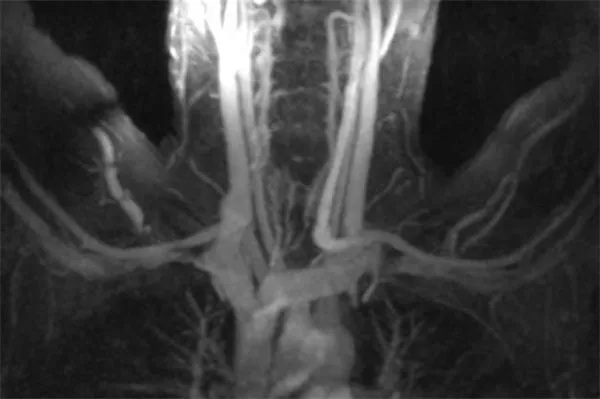

Therefore, after the physician makes the initial diagnosis of venous TOS, imaging diagnosis of venous TOS serves several purposes. Firstly, imaging tests confirm the presence and extent of venous blood clot. Secondly, imaging tests clarify the extrinsic structures compressing the vein. Thirdly, imaging tests show the intrinsic damage to the vein. It is important to realize that arm motion forwards or over the head causes vein compression in many people. Therefore, experts perform imaging tests with the arms down and with the arms elevated.

MR venography (MRV) can be performed in two ways. First is direct MRV. The physician injects contrast into a small arm vein. Shortly thereafter, the MRI scanner creates images as the contrast passes through the arm and chest. Direct MRV shows only veins, and only in one arm. In contrast is indirect MRV. Again, the physician injects contrast into a small arm vein. In contrast to direct MRV, scanning begins after a delay. First, injected contrast travels through the heart, the lungs, the arms, and returns through the arm veins. At this time, the MRI scanner creates images, showing both arteries and veins, in both arms. MRV shows the veins while eliminating other structures. MRV requires no radiation. If used in conjunction with MRI, superb soft tissue detail is available. Excellent depiction of fibrous bands, muscle anomalies, bones, and brachial plexus is possible with the combination of MRV and MRI.

This patient had an MR angiogram, followed by an MR venogram. Slide the handle side to side to see the difference between the two studies.